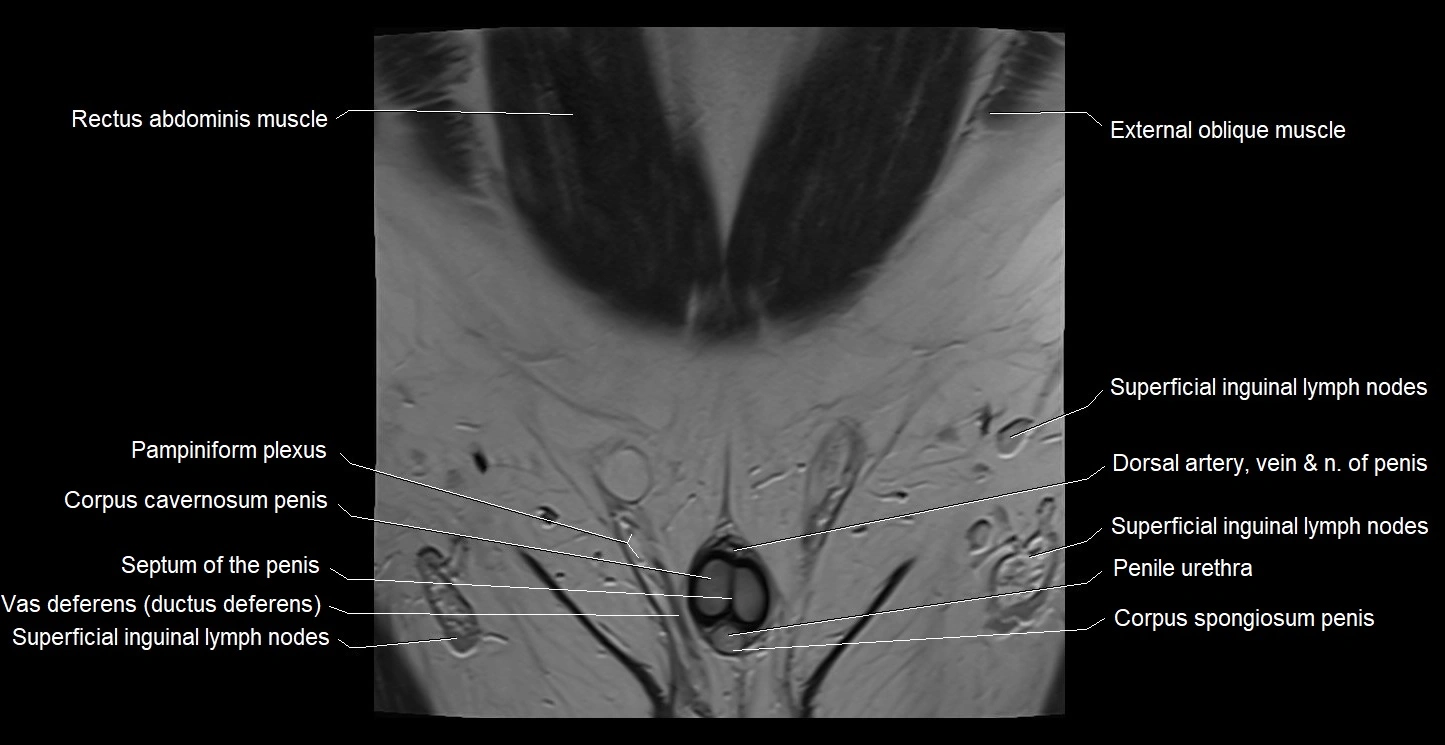

- Pampiniform plexus

- Penile urethra

- Septum of the penis (Penile septum)

- Superficial inguinal lymph nodes

- Vas deferens